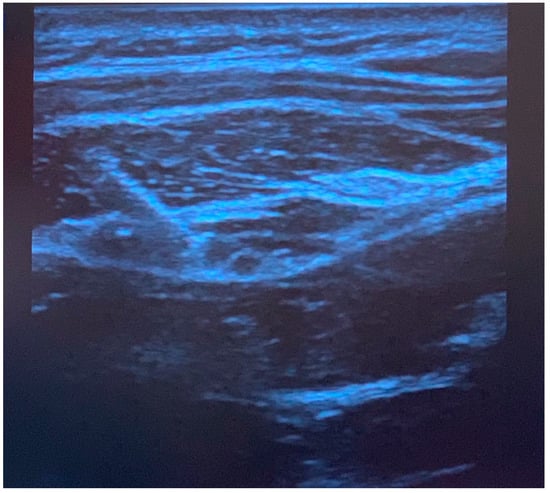

Greater occipital nerve blocks were performed following induction of anesthesia, prone positioning, and sterile preparation. To perform the blocks, a linear ultrasound probe was used to locate the C2 spinous process, and the probe moved laterally and rotated (Figure 1) to find the obliquus capitis inferior muscle plane (Figure 2) as previously described [6]. Blocks were performed with 0.2% ropivacaine, with volume and additives determined by the anesthesiologist. Prior to incision, additional injections of epinephrine with or without local anesthetic were performed at the incision site by the surgical team for hemostasis. Intraoperative analgesic and sedative adjunct usage was determined by the anesthesiologist. Further details of intraoperative characteristics and intraoperative medications can be found in Table 1.

Figure 1. Performance of a right greater occipital nerve block at the C2 level. The probe is lateral and slightly rotated for an in-plane approach.